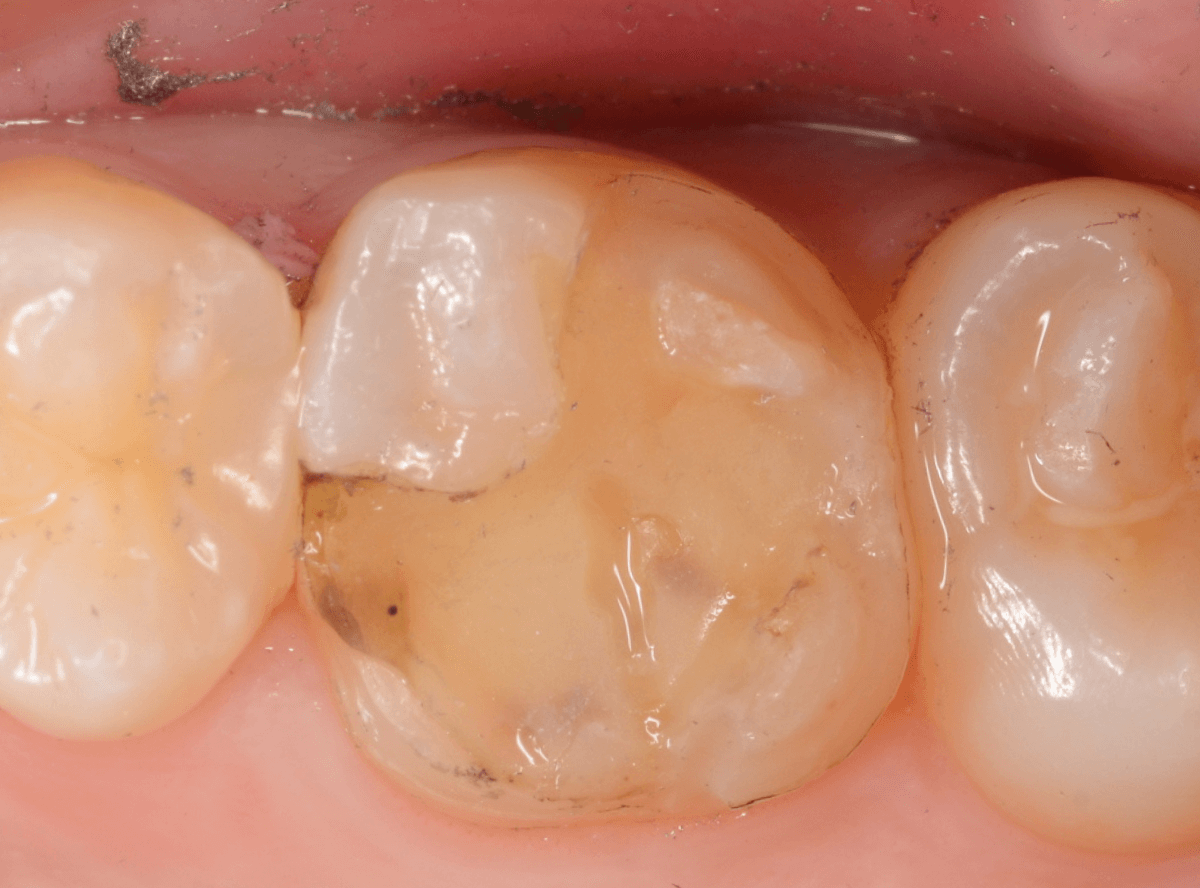

さし歯の土台の補修と、おやしらずの虫歯の処置をしたところです。

この状態で型をとります。

治療前後の比較写真になります。